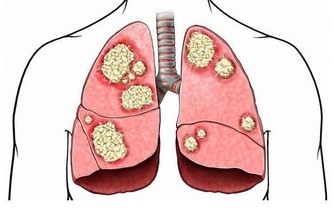

*****4. 糞便很細,排便不爽*****

一旦持續一段時間排出的均為柔軟的細便,並且總有排不盡的感覺,要特別注意,需要接受內鏡檢查。